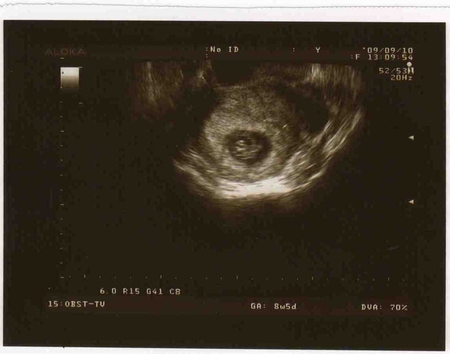

Результаты: УЗИ, КТГ, доплера, скринингаНЕ могла больше терпеть, сбегала сегодня на Узи:)) Все у нас хорошо:)) Плод один, сердцебиение хорошее, угрозы нет:))) Я хоть немного вздохну без переживаний

дали фото, правда там почти ничего не понятно:)) Но это не главное!